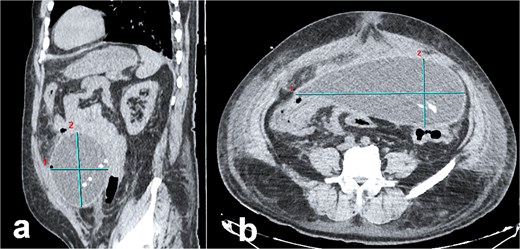

Abdominal computed tomography (CT) demonstrated a large encapsulated cystic mass (9.98 × 12.8 × 23.35 cm) in the abdominal cavity. The lesion adhered to the posterior surface of the anterior abdominal wall, enveloped the dialysis catheter tip, and contained fluid (Fig. 1a and b). Exploratory laparotomy via a midline infraumbilical incision revealed a 20 × 15 cm preperitoneal pseudocyst with dense adhesions to peritoneal tissue and small bowel loops (Fig. 2a and b). The cyst was incised, yielding copious serous fluid, and the entire capsule was excised. The dysfunctional dialysis catheter was concurrently removed. Gross examination identified an irregular peritoneal cyst fragment (14.0 × 18.7 cm) with a pinkish-yellow hue and rubbery consistency, alongside a smaller nodular fragment (4.0 × 3.5 × 2.0 cm). Microscopic analysis revealed adipose tissue with extensive fibrosis and fibroblastic proliferation.

Abdominal CT imaging of peritoneal pseudocyst. (a) Sagittal view: The dialysis catheter tip (arrow) is visualized within the pseudocyst. Note collapsed small bowel loops displaced into the retroperitoneum. (b) Axial view: Encapsulated pseudocyst with thick, enhancing walls (asterisk), and homogeneous serous fluid content. Bowel loops are displaced posteriorly into the retroperitoneum.